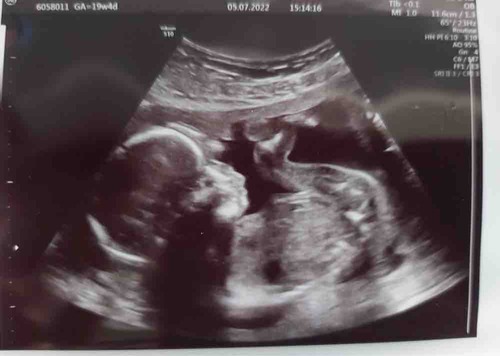

Ja alles is helemaal goed. Ondertussen bijna 20 weken zwanger van onze klei ...